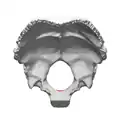

![]() Потилична кістка згори. Отвір, позначений стрілкою - foramen magnum | |

![]() Внутрішній бік потиличної кістки з великим отвором. Малюнок з «Анатомії Грея» | |